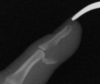

What is this?

Jersey Finger

Avulsion injury of Flexor Digitorium Profundus

What flexor tendon zoneof injury is this?